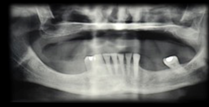

The aim of this workshop was to assess the posterior maxillary area. The posterior maxilla naturally presents low-height alveolar process, which is anatomically limited by the maxillary sinus. The roots of the molars are closely related to the floor of the maxillary sinus. In the center of the alveolar crest we find the root trifurcation area, which is the ideal site for implant placement from a prosthetic perspective, and where there is the lowest bone height in the sinus floor. This means that placing implants of standard dimensions after tooth loss

in this area is limited.

The resorption processes resulting from such loss, common to all regions of the alveolar process, may aggravate this situation. Maxillary sinus pneumatization, on account of increased osteoclastic activity along the sinus membrane and the absence of a dental “barrier” facing changes in sinus air pressure, may affect the morphology of the site. These conditions pose an anatomical challenge to the treatment of the edentulous posterior maxilla using dental implants. The techniques to repair defects in the residual alveolar ridge with autologous bone graft procedures have predictable results, which are described in the literature. A factor that explains their good results is that there are no immune reactions that may interfere with the process of tissue remodeling and development. They intrinsically have osteoblasts and growth factors responsible for the cellular changes that occur after implantation, and that end with remodeling and bone formation at the site1. Its disadvantage is the need for an additional donor surgical area which can be intraoral, in cases in which the need for reconstruction is small, or extraoral in cases of medium-sized or large reconstructions. In the 1980s, bone grafting techniques in the maxillary sinus were used to solve the problem of lack of bone, and to allow for implant placement. One of the techniques described is surgery to lift the floor of the maxillary sinus, known by its name in English: Sinus Lift2,3.

Question No. 1. Short implants or maxillary sinus lift? Which technique is more predictable according to the literature? According to the literature studied, the maxillary sinus lift technique is better documented, showing long-term implant survival rates. However, there are possible complications, such as: sinusitis (3%) and infections (1%), in addition to a higher morbidity. This makes it relevant to evaluate other techniques, which show similar results5. Currently, the use of short implants (less than 8 mm) is a practice that in the last six years (medium term) has acquired sufficient scientific support to be applied, depending on the clinical situation6,7,8.

Question No. 2. Indications and factors to consider to perform a lateral approach maxillary sinus lift.

Reduced subantral bone height (5 to 8 mm) is required. Less invasive and simpler techniques are needed for specific reasons, such as: systemic problems, psychological profile or patient’s choice.